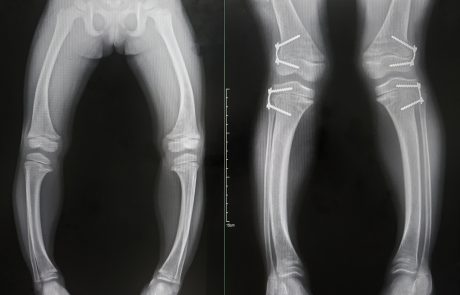

„XLH-Betroffene brauchen eine adäquate Betreuung – Ihr Leben lang“

LEBEN MIT XLH: „Eine kontinuierliche Behandlung ermöglicht ein enormes Plus an Lebensqualität und Teilhabe“